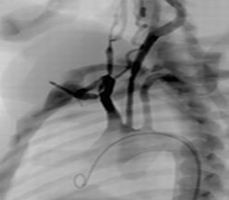

頸動脈介入手術(shù)模塊

可練習(xí)頸動脈支架手術(shù)的完整過程:造影診斷、導(dǎo)絲通過、導(dǎo)引導(dǎo)管的放置、保護(hù)傘的放置、預(yù)擴張、自擴張支架放置、后擴張、以及再造影等。